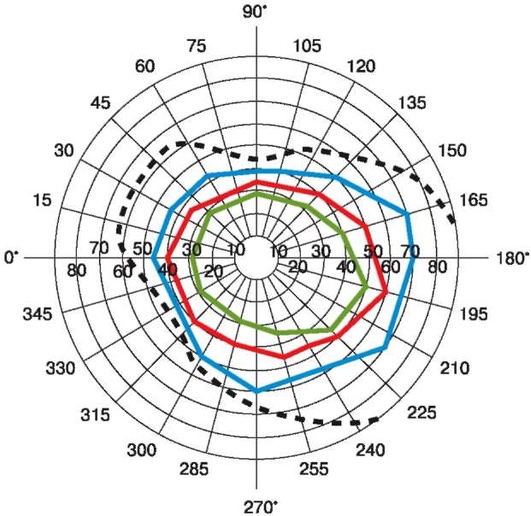

Рис. 13.1. Нормальное монокулярное поле зрения на белый свет и цвета. Пунктиром изображено поле зрения на белый цвет, цветными линиями - на соответствующие цвета